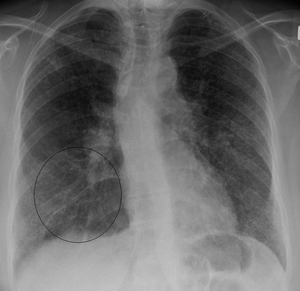

| Chest X-ray showing the typical nodularity of sarcoidosis in the base of the lungs. | |

Sarcoidosis is a disease involving abnormal collections of inflammatory cells that form lumps known as granulomas.[1] The disease usually begins in the lungs, skin, or lymph nodes. Less commonly affected are the eyes, liver, heart, and brain. Any organ, however, can be affected. The signs and symptoms depend on the organ involved. Often there are no, or only mild, symptoms.[1] When it affects the lungs there may be wheezing, cough, shortness of breath, or chest pain.[2] Some may have Lofgren's syndrome in which there is fever, large lymph nodes, arthritis, and a rash known as erythema nodosum.[1]